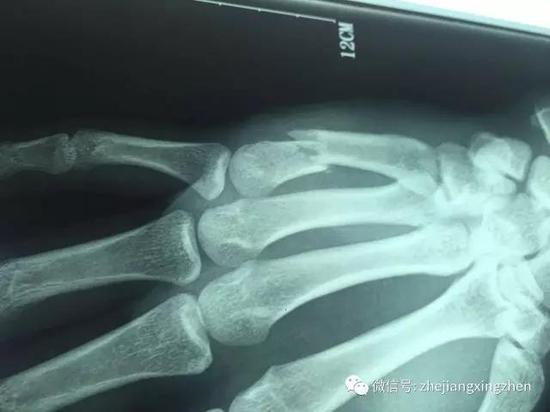

临沂小伙工作中意外受伤 手掌断成两截

640x360 - 134KB - JPEG